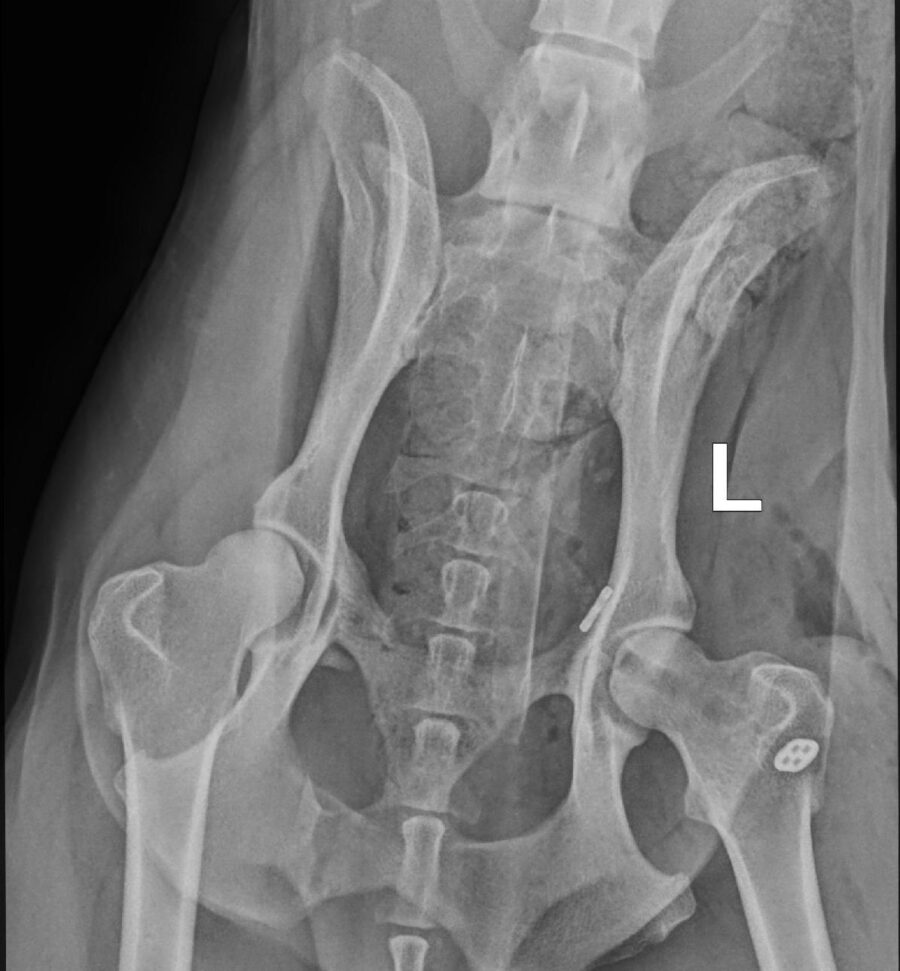

• Fracturen met platen, schroeven of pinnen

• Heupkopresectie